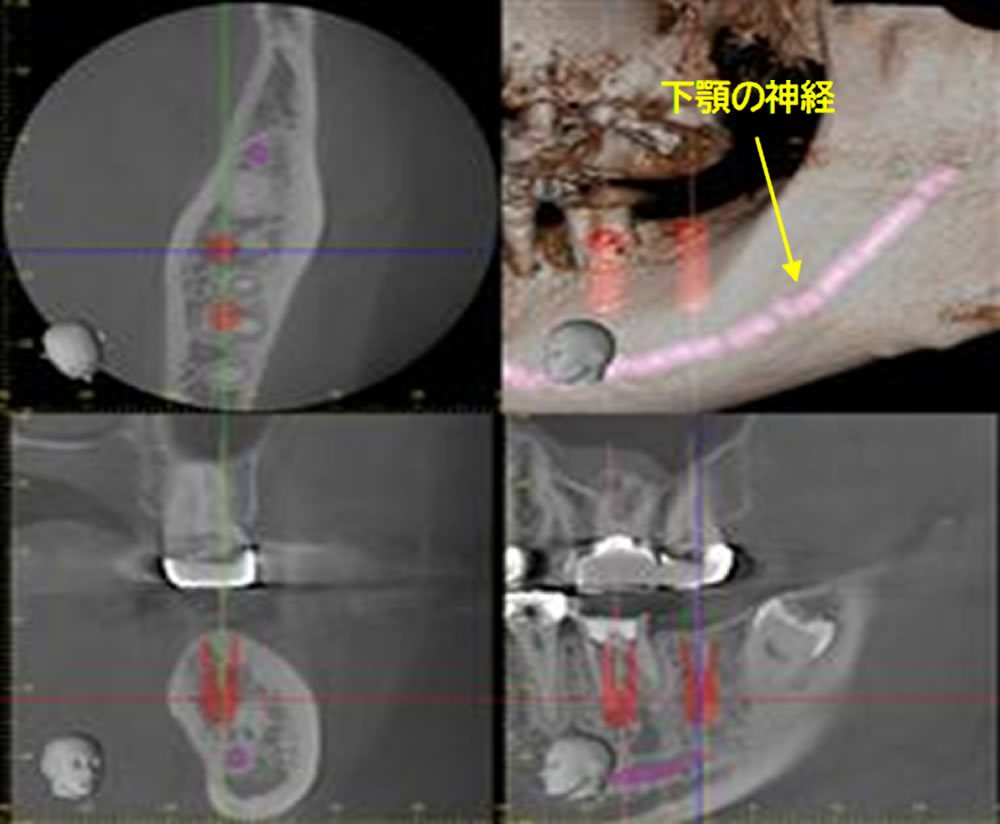

インプラント埋入のシミュレーション

CT上でインプラントを埋入した際のシミュレーションを行いました。神経までの距離を測り、患者様に合わせたサイズのインプラント体を選択します。

下顎の神経(下顎管)とインプラント埋入時の位置は問題なく、手術が行えると判断しました。カウンセリングにて、治療方法・治療期間・手術のリスク・費用・注意事項の説明を致します。